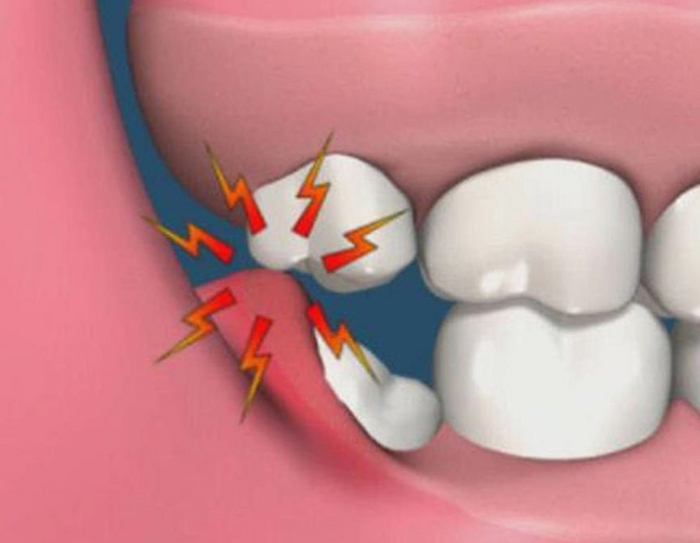

Самое главное, чтобы в процессе удаления зуба не прилагалась большая сила. Потому что если мы будем прилагать большое усилие при извлечении зуба их кости, то в лучшем случае мы обломаем корни и будем возиться целый час с ними, а в худшем, вывихнем соседний зуб, а если врач весь интеллект перекачал в силу, то и перелом челюсти. Те, кто считает, что для удаления зубов нужна сила глубоко заблуждаются. Девочка метр с кепкой и в прыжке может удалять зубы в 100 раз быстрее, безболезненнее и аккуратнее, чем амбал. Тут главное мозг и аккуратность.